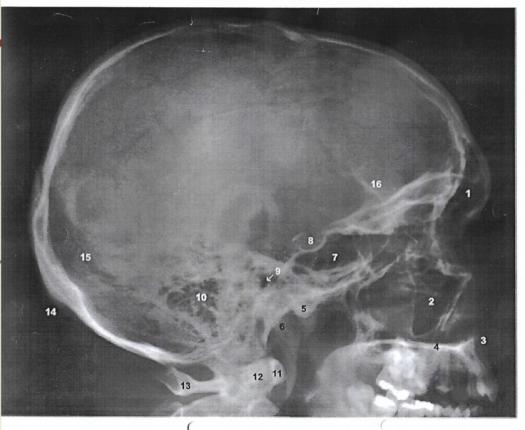

39. The part number 6 represents :

Explanation

The part number 6 represents the lambdoid suture. The lambdoid suture is a dense, fibrous connective tissue joint that connects the parietal bones of the skull to the occipital bone at the back of the head. It is named after its shape, which resembles the Greek letter lambda (Λ). The lambdoid suture helps to provide stability and strength to the skull, as well as allowing for some flexibility during childbirth.

40. Where we can find the Anterior nasal spine ?

The correct answer is A. The anterior nasal spine can be found in the nasal cavity, specifically at the junction of the maxilla and the nasal bone. It is a small projection that helps to support the nasal cartilage and provides stability to the nasal septum.

37. What number represents the odontoid process of axis ?

The odontoid process of axis is represented by the number 12. The odontoid process is a bony projection that extends upward from the body of the axis vertebrae, also known as the second cervical vertebrae. It serves as a pivot point for the rotation of the atlas (first cervical vertebrae) and allows for the movement of the head.